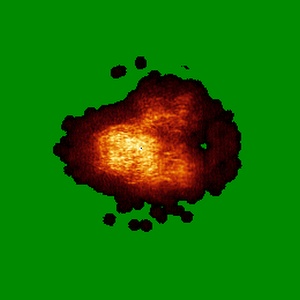

Major cryo-EM structure of S protein trimer of SARS-CoV2 with K-874, composite map

Single-particle3.9 Å